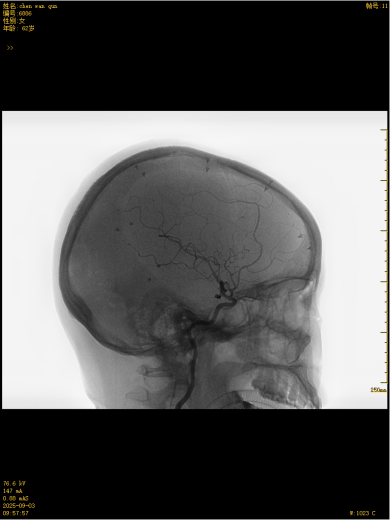

这款国产创新技术的优势不止于疗效:通体显影设计让支架定位精准到毫米级;超弹性材质与优化编织工艺实现极致贴壁,兼顾支撑力与柔顺性,适配复杂迂曲脑血管;操作更轻巧、创伤更小,仅需大腿根部米粒大小切口即可完成手术,可实现患者术后可快速康复。本次手术中,团队在DSA引导下精准释放支架,全程耗时短、出血少,术后造影显示,动脉瘤内血流即刻变得迟缓,载瘤动脉通畅,重要分支血管保护完好。患者术后恢复良好,未出现任何神经功能障碍,术后不久即快速康复出院,重获健康,恢复正常生活工作。